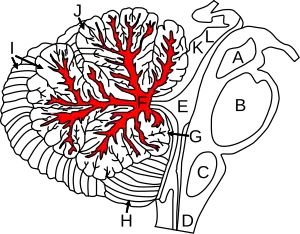

Figure shows cerebellum and surrounding regions; sagittal view of one hemisphere. A: Midbrain. B: Pons. C: Medulla. D: Spinal cord. E: Fourth ventricle. F: Arbor vitae. G: Flocculus. H: Tonsil. I: Posterior lobe. J: Anterior lobe. K: Inferior colliculus. L: Superior colliculus. | |